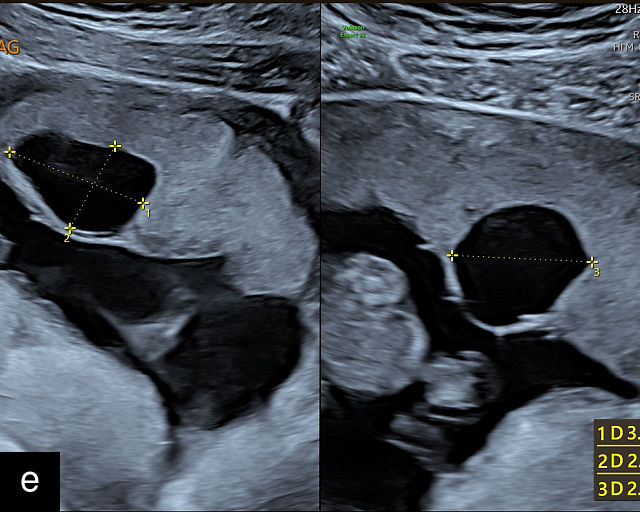

Placental chorioangiomas

The typical sonographic appearance of a chorioangioma on grayscale ultrasound is a well-circumscribed mass arising from the fetal surface of the placenta, protruding into the amniotic cavity, and distinctly separate from the placenta (Figure 12; Video 7). These tumors are most commonly located near the umbilical cord insertion site on the placenta. Sonographically, they may appear hypoechoic or hyperechoic and are often heterogeneous, with possible calcifications, hemorrhage or infarction visible within the mass.9 The appearance of these masses may change over time.141 Color flow Doppler imaging typically reveals vascularity within the tumor, showing low-resistance vessels and arteriovenous shunts (Figure 12c–e; Video 7).9 These shunts are believed to contribute to fetal complications such as high-output cardiac failure, anemia and hydrops.141 Three-dimensional ultrasound may be helpful in assessment of the mass.146 Importantly, the differential diagnosis includes placental hemorrhage, and color flow Doppler is essential to assist in making the diagnosis.

12

Grayscale (a,b), color Doppler (c,e) and power Doppler (d) images of chorioangiomas, showing heterogeneous masses protruding from the placental surface.